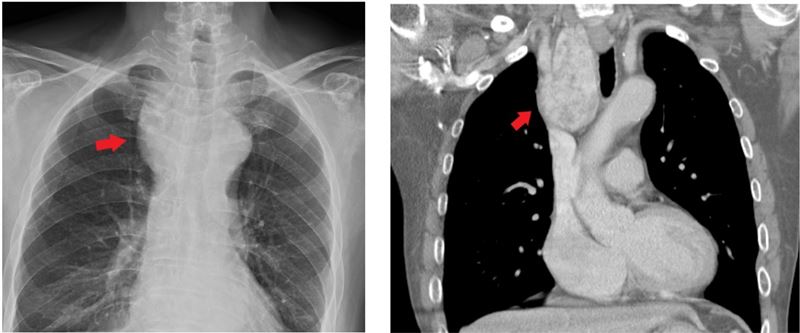

一名60歲男長期胸悶、呼吸不順,檢查發現甲狀腺腫塊壓迫氣管。(圖/聯新國際醫院提供)

聯新國際醫院甲狀腺外科林晏甥醫師分享案例,一名年約60歲男性長期胸悶、呼吸不順,平躺時還會感覺「吸不到空氣」,隨即就醫,透過胸部X光檢查發現,氣管右側有疑似腫塊陰影,造成局部氣管偏移中線。進一步電腦斷層掃描發現,一顆由甲狀腺右葉延伸到胸腔內、約為9×5公分如鵝蛋般大小的腫大結節,已明顯壓迫氣管,當時被建議手術切除。